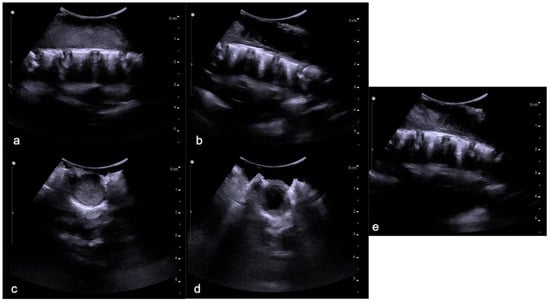

4.1. Hemangioblastomas